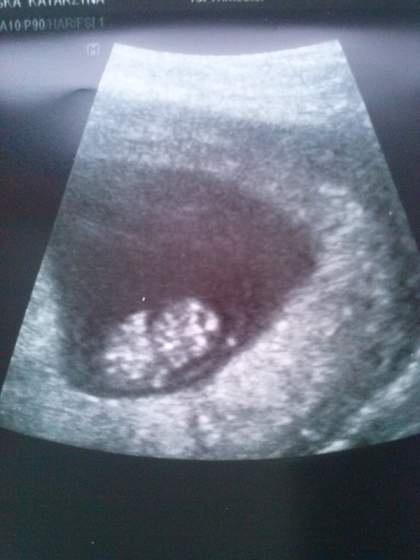

Przedstawiem Wam nasze 1,93cm szczęścia. Ma pięknie mrugające serduszko :-) Wszystko jest w najlepszym porządku, ufff ;)

Kolejną wizytę mamy za miesiąc. Mam mieć badania genetyczne.

Mam już kartę ciąży i w poniedziałek idę na krew i mocz. No to chyba na tyle.